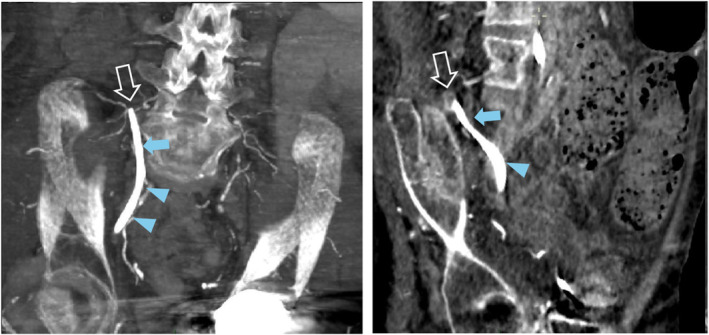

隧道式透析导管是无法从动静脉瘘中获益的透析患者的替代选择。这种导管的插入通常在超声引导下进行,以防止并发症的发生。一名 36 岁的患者在插入右股静脉隧道式透析导管后出现了意想不到的并发症:虽然导管插入后采集的血液是静脉血,但在开始持续肾脏替代疗法(CRRT)几分钟后,血液变成了动脉血。停止治疗后,血液又变成了静脉血。第一个不太可能的假设是导管位于动脉。但事实证明并非如此。我们将介绍此类病例的处理方法。

Tunneled dialysis catheter is the alternative for dialysis patients who cannot benefit from an arteriovenous fistula. The insertion of such catheters is usually ultrasound-guided to prevent complications. A 36-year old patient had an unexpected complication following the insertion of a right femoral tunneled dialysis catheter: Although the blood collected from the catheter was venous after insertion, the blood turned arterial few minutes after initiating a continuous renal replacement therapy (CRRT). It became venous again after stopping the therapy. The first, yet unlikely hypothesis, was an arterial location of the catheter. In fact, it turned out not to be. We describe the management of such a case.